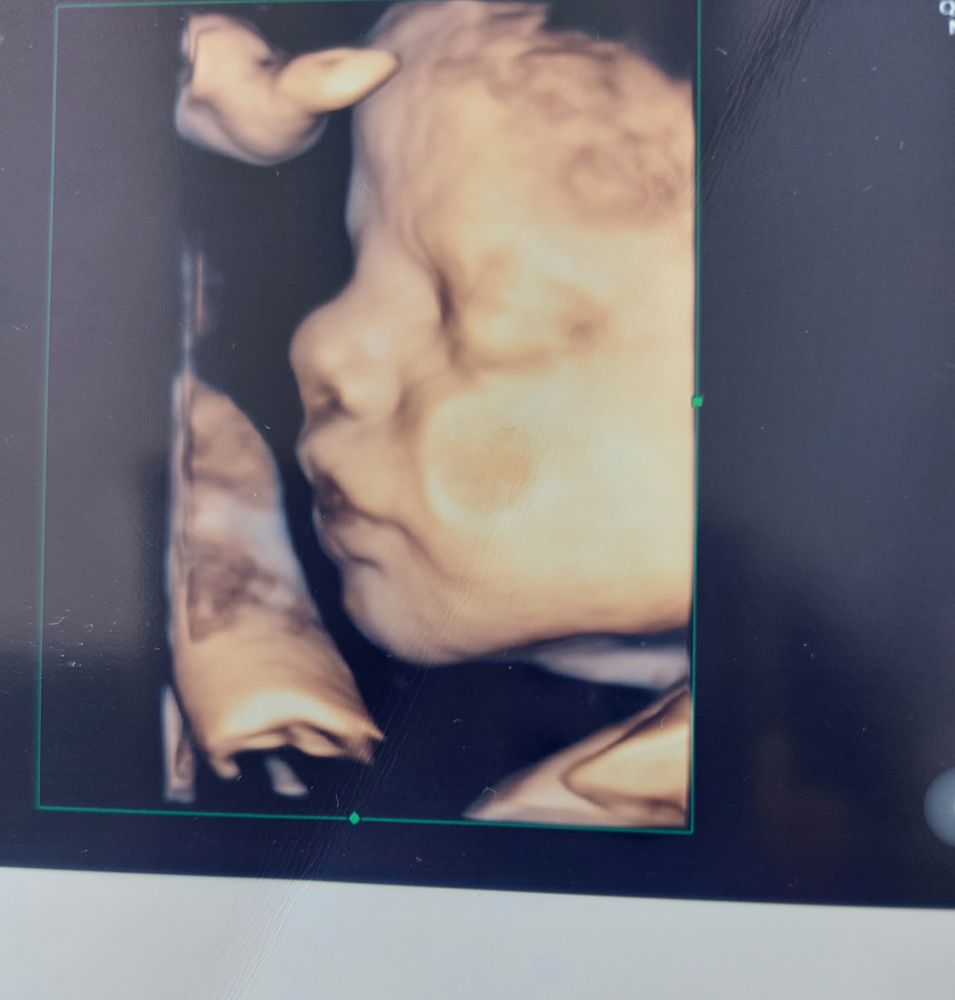

4 D узи

На 32 делала фото и видео

Личико видно на любом сроке, но щëчки пухленькие недели на 32 лучше смотреть 🥰